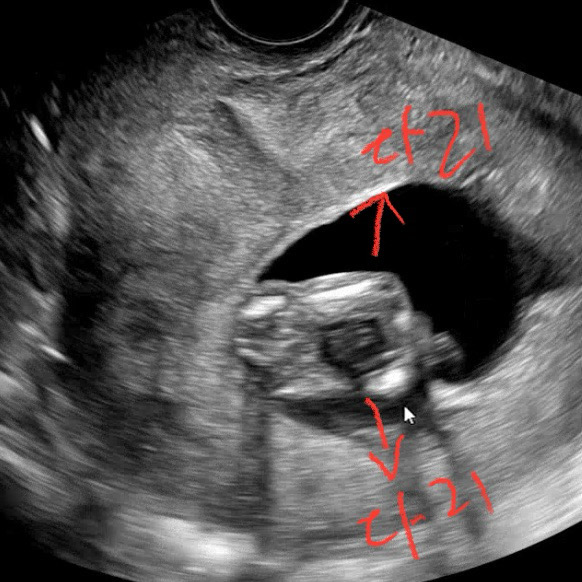

아기 가랑이 사이 같이 봐주세요🤣

제가 봤을 때는 매끈한거 같은데 어떠신지 다들 참견 많이많이 부탁드려요🙏

딸같아요~~

딸같아료 아무것도 안보이네용ㅇㅇ